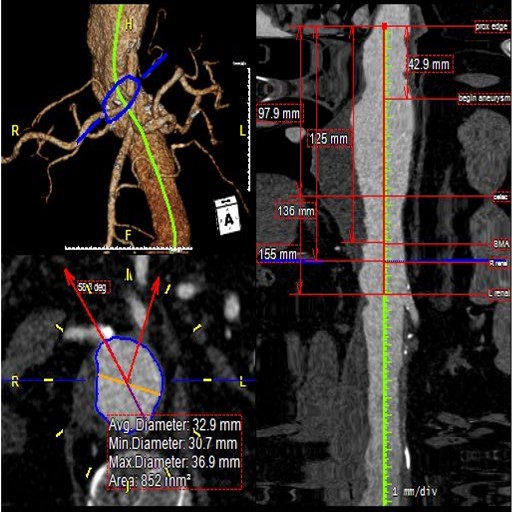

Using the most advanced, three-dimensional reconstruction

software, a custom-made endograft is planned and designed

for your patient’s specific anatomy.

About Fenestrated and Branched Endografts

For complex aneurysms (those aneurysms which include portions of the aorta with branch arteries that supply organs such as the kidneys and intestines), a special type of repair is required to preserve flow to these branch arteries: a fenestrated endograft, with special holes placed in the endograft at the precise location in which these branches arise. The fenestrated endograft is designed specifically to fit each patient’s particular anatomy; this is possible through the use of sophisticated imaging software that allows Dr Schanzer and his team to manipulate the CT images obtained of the patient’s aorta and branch arteries.